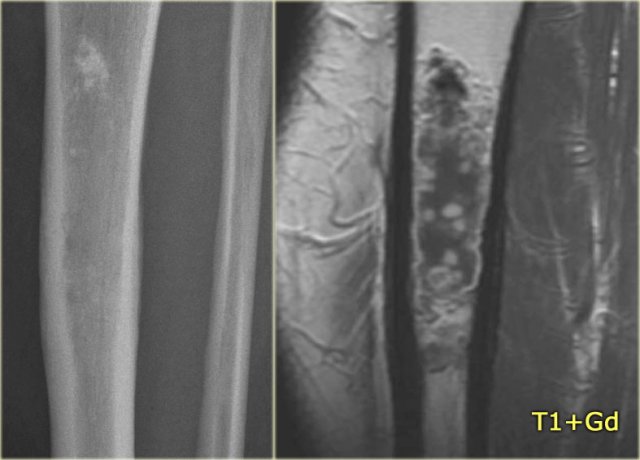

ABC (6) - atypical case

On the left two different patients with an intracortical or subperosteal osteolytic well-defined lesion in the tibia.

The lesion on the far left was thought to be an adamantinoma because of the localisation in the anterior tibial cortex.

At biopsy it proved to be an ABC.

The image on the right is an adamantinoma.